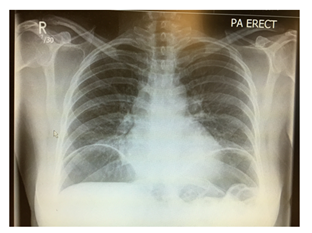

Case Presentation: 42-year-old female presented to Accident and Emergency (A&E) department with severe abdominal pain and chest X-ray showed (Figure 1) free gas under the diaphragm. She was known to have irritable bowel disease (constipation predominantly). She had an urgent laparotomy. Thorough examination of all internal organs was conducted but no abnormality was found.

Figure 1 Chest X-ray showed air under the diaphragm.

Her inflammatory markers were raised with C reactive protein (CRP) reading at 150 mg/L and White cell count of 10.2X 109. Erect chest X-ray showed large amount of air under the diaphragm and abdominal X-ray showed dilated small bowel loops (Figure 2) in the left upper quadrant and free air between the loops. The patient underwent emergency laparotomy with hissing of air escape at peritoneal opening. All organs were examined and no abnormality was seen. All four quadrants examined thoroughly but no evidence of any bowel leak found. There were no signs of any inflammation in pelvis and a negative laparotomy was concluded. The patient had uneventful recovery and was discharged home on 4th post-operative day. The patient underwent further abdominal and pelvic CT scan Figure 3-5 with contrast few days after the operation for completion of investigation and no abnormality was seen. The patient was reviewed in the clinic one and three months after the operation with no complaint and no post-operative complications.